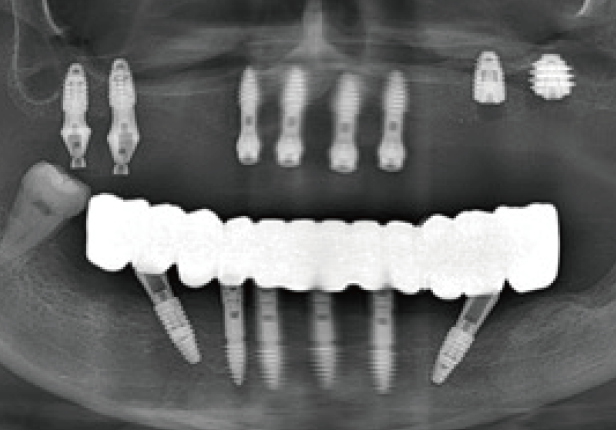

Panorâmica pré-cirúrgica

Panorâmica pós-cirúrgica

Panorâmica Final da Coroa

Panorâmica Pós-Cirúrgia